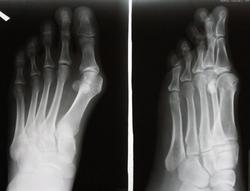

Пол пациента: Женский пол Тип патологии: Другое Область исследования: Скелетно-мышечная система Методы исследования: Rg Hallus valgus 1 пальца левой стопы. Как грамотно описать? ID:24084